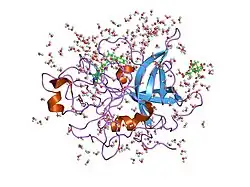

Structure

Urokinase is a 411-residue protein, consisting of three domains: the serine protease domain (consisting of residues 159–411), the kringle domain (consisting of residues 50-131), and the EGF-like domain (consisting of residues 1-49). The kringle domain and the serine protease domain are connected by an interdomain linker or connecting peptide (consisting of residues 132–158). Urokinase is synthesized as a zymogen form (prourokinase or single-chain urokinase), and is activated by proteolytic cleavage between Lys158 and Ile159. The two resulting chains are kept together by a disulfide bond between Cys148 and Cys279.[9]